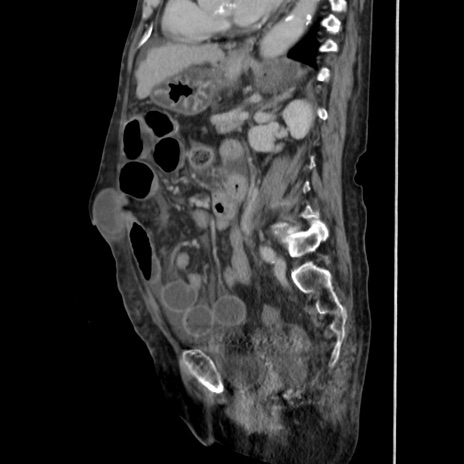

症例31(矢状断像)

【症例】80歳代 女性

【主訴】腹部膨満感

【現病歴】他院にて肝硬変にてフォロー中。1週間前から便秘、腹部膨満感、臍部腫瘤あり受診となる。

【既往歴】肝硬変

【身体所見】腹部膨隆あり、皮膚変化なし、疼痛なし。

【データ】WBC 4600、CRP 0.25